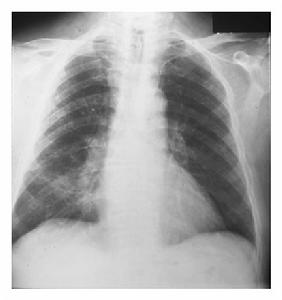

非特異性間質性肺炎影像學特點:高分辨CT顯示雙肺對稱性毛玻璃影或雙肺肺泡腔的實變影。

非特異性間質性肺炎底片對NSIP病人的BALF檢查發現細胞總數明顯增多,平均(4.4~4.5)×108/L;其淋巴細胞所占比例通常明顯高於UIP的病例,平均為37.7%~42.7%。本文3例的BALF淋巴細胞均升高,第2例淋巴細胞甚至占90%。最近Nagai等[4]報導,對NSIP患者BALF中T淋巴細胞亞群分析發現CD4/CD8比例明顯下降,在以炎症成分為主而纖維化較少的病例中,更可降至0.3;而在UIP這一比例平均值為1.65。我們對第2、3例進行了BALF的T淋巴細胞亞群分析,結果也是CD4/CD8明顯倒置,分別為0.25和0.227。這種T細胞亞群的變化頗令人感興趣,至於它對鑑別診斷的意義以及對判斷炎症程度與治療反應等方面的價值尚有待於進一步研究。

電子顯微鏡鏡下肺炎支原體三、咳嗽以夜間為重,偶爾有少量黃粘痰,入院前1個月出現活動後氣短,漸加重至上一層樓梯亦有症狀,同時伴胸背持續鈍痛。病程中有間斷髮熱,無關節肌肉痛史。體格檢查:輕度紫紺,無杵狀指,雙肺可聞爆裂音。血ANA、抗ds-DNA、RF及抗ENA均陰性。胸片示雙中下肺間質紋理厚,呈磨玻璃樣改變伴小斑片結節狀影。HRCT(圖4)見右肺中葉、左肺舌葉及雙肺下葉密度增高呈磨玻璃樣改變,雙肺支氣管血管紋理增厚,右肺中葉內側段支氣管擴張,雙側胸膜不規則增厚,縱隔內及雙肺門淋巴結多發鈣化。血氣分析PaO261.4mmHg。BALF細胞總數1.27×109/L,淋巴細胞占32%,中性細胞占47%,巨噬細胞占21%;T淋巴細胞亞群分析:CD417.6%,CD877.7%,CD4∶CD8=0.227。經支氣管肺活檢(TBLB)病理所見為少許血管及破碎的支氣管黏膜上皮呈急性及慢性炎。經電視引導下胸腔鏡肺活檢確診為非特異性間質性肺炎。

2.HRCT的主要特徵是:雙側、對稱、主要在下肺的網狀陰影,伴牽拉性支氣管擴張和下葉體積減少,通常為瀰漫性或胸膜下分布,但有時病變並不累及胸膜下肺組織。